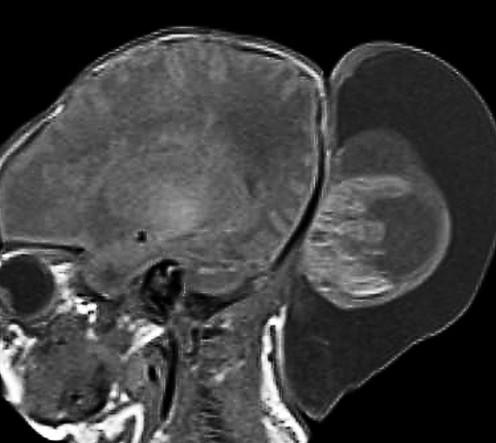

Differential for “cyst in the posterior fossa” starts with whether the vermis is normal or not.

Is the vermis normal? Can you identify the normal structures of the Vermis?

Malrotated hypoplastic vermis, with vertical primary fissure.

“OPEN” fastigial point of the fourth ventricle. Hypoplastic cerebellar hemispheres.

Enlarged posterior fossa

Cystic dilatation 4th ventricle

Uplifted tentorium, TSV sinus, torcula

“torcula-lambdoid inversion” with torcula above the lambdoid suture

Agenetic or hypogenetic vermis with “vermian tail, pushed upward

Cerebellar hypoplasia

CC anomalies 32%

Hydrocephalus up to 90%

Aqueductal stenosis

4th ventricle outlet obstruction

Polymicrogyria, heteropia 5-10%

Occipital Meningo-Encephaloceles 16%

Syndromic = Extracranial anomalies 50%